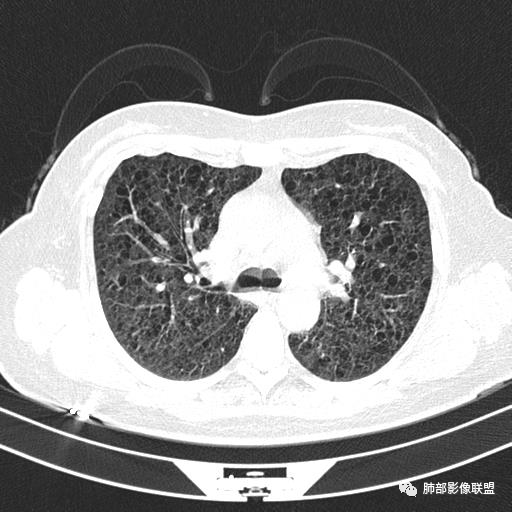

中年女性,不吸烟

双肺弥漫囊腔,累及肋膈角,囊腔形态相对规则单一。

CT平扫示双肺弥漫分布大小不等囊状薄壁透光区,无内、中、外带分布差异,间质稍示增厚。拟LAM

中年女性育龄期妇女,咳嗽气喘,无吸烟史,有苯吸入史。影像:双肺弥漫均匀小囊腔,无明显分布优势,囊腔形态欠规则,壁薄,部分囊腔边缘血管征,伴双肺弥漫磨玻璃影,无结节,考虑lam,鉴别苯中毒肺损伤,囊腔多有分布优势,小叶中心分布为主,形态规整等

中年女性,两肺弥漫分布囊性低密度影,壁薄,相对规则,境界尚清晰,考虑LAM

中年育龄期女性,双肺多发含气囊腔弥漫性分布,囊间肺组织结构正常,常规考虑Lam

双肺弥漫大小不一薄壁含气囊腔,囊间肺组织正常,正常肺背景,肺尖肺底受累;青年女性,气喘,支持LAM

CT表现:双肺弥漫大小不等的薄壁囊腔,囊壁<2mm,外形规则,血管影多位于囊腔周围,囊腔之间肺组织正常,随着疾病进展到晚期,囊腔变大、增多,不可胜数,囊腔可融合成较大的囊,与肺气肿相似,形成间质性肺纤维化。部分病例可出现结节影。